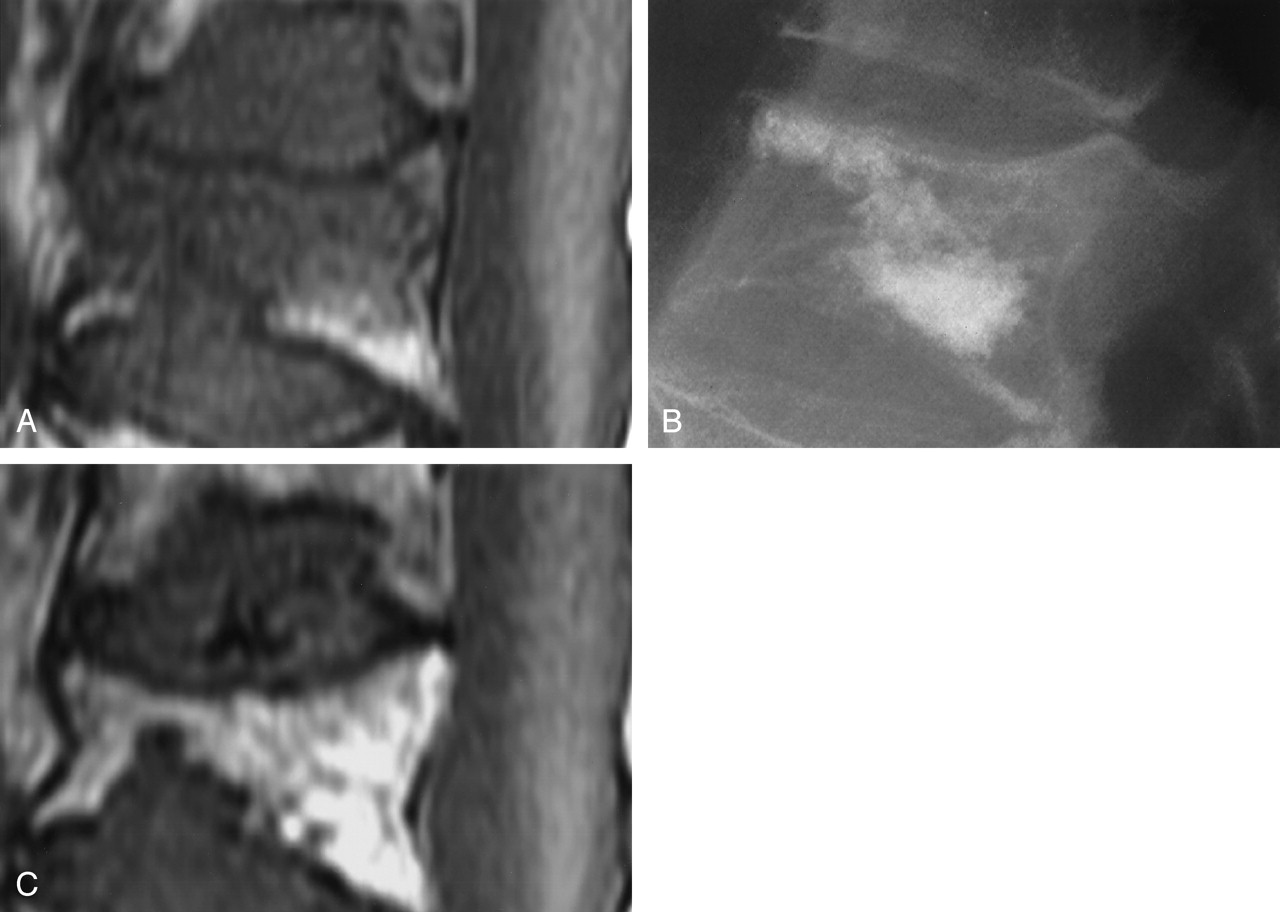

Persistent marrow edema after VP.

A, Preprocedure T1-weighted MRI shows partial compression of T8 with severe edema.

B, Lateral radiography at time of VP shows cement filling an intravertebral cleft and adjacent marrow.

C, T1-weighted MRI 1 year after VP shows persistent severe edema as well as a new compression fracture of T9.

To describe the correlation between marrow edema score and time interval between VP and follow-up MRI, we reviewed the additional follow-up MRIs in patients who returned again during the study interval. Including all follow-up MRIs during the study interval, and the additional vertebrae treated, there were 81 MRIs of 61 treated vertebrae in our 30 patients. These MRIs were categorized by time interval after VP: 0–6 weeks, 6 weeks to 3 months, 3–6 months, and >6 months. In the early follow-up interval (0–6 weeks), 15 of 24 (63%) vertebrae had moderate or severe edema. As follow-up interval increased, the number of vertebrae in the moderate and severe marrow edema categories decreased, but not to 0. Of vertebrae imaged >6 months after the VP, five of 23 (22%) still had moderate or severe edema (Figs 3,4).

Increased T2 marrow signal intensity in compressed vertebrae is associated with acute or subacute fracture and incomplete healing, with normal signal intensity expected after 1 month of normal healing (11). Our study demonstrates that marrow edema in vertebrae treated with VP may persist for 6 months or longer. Further, we noted that previously normal marrow became edematous after VP in 19% of cases. Although marrow edema tended to decrease with increasing follow-up intervals, 22% of vertebrae had either moderate or severe edema at >6 months of follow-up. This suggests that even persistent marrow edema in previously treated vertebral bodies should not be taken as evidence of unsatisfactory operative result or of ongoing pain.